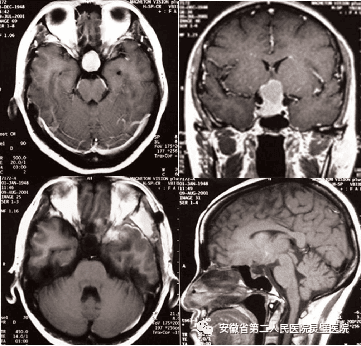

二、神经肿瘤的综合治疗技术

常规开展各型颅内及脊髓肿瘤手术,包括鞍区肿瘤、斜坡肿瘤、后颅窝等颅底肿瘤,尤其在听神经瘤、颅咽管瘤、垂体瘤等治疗方面处于国内领先水平。系统开展胶质瘤的综合治疗,并结合肿瘤基因指标,提升胶质瘤的放化疗效果,极大提高5年的存活率。

岩斜区脑膜瘤术前及术后